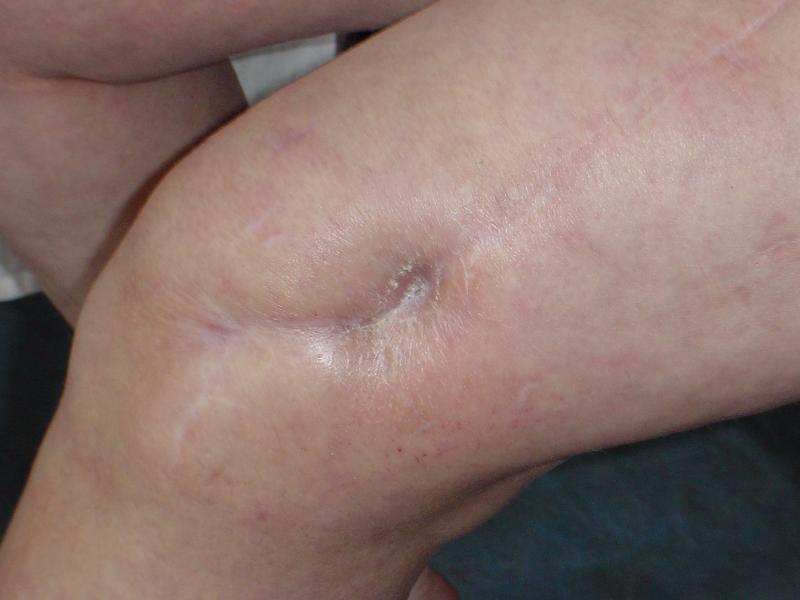

В 2002 г. была у нас больная с ложным суставом бедра и остеомиелитом (как оказалось), после удаления пластины. Гвоздь с блокированием.

Потекло через месяц - открылось 2 свища по старому рубцу от давно удаленной пластины. На фоне гноя раза три завинчивал обратно винты, которые вылезали латерально, прямо через свищ. Потом таки провел дополнительно винты мимо гвоздя, и убрал вверху статический винт. Острый гнойный процесс стих, свищи мыла она дома дважды в день водным хлоргексидином, ходила с возрастающей нагрузкой, а к 10 мес. и свищи закрылись, и срослось. Итоговые снимки от 18 апреля 2003 г. прилагаю.